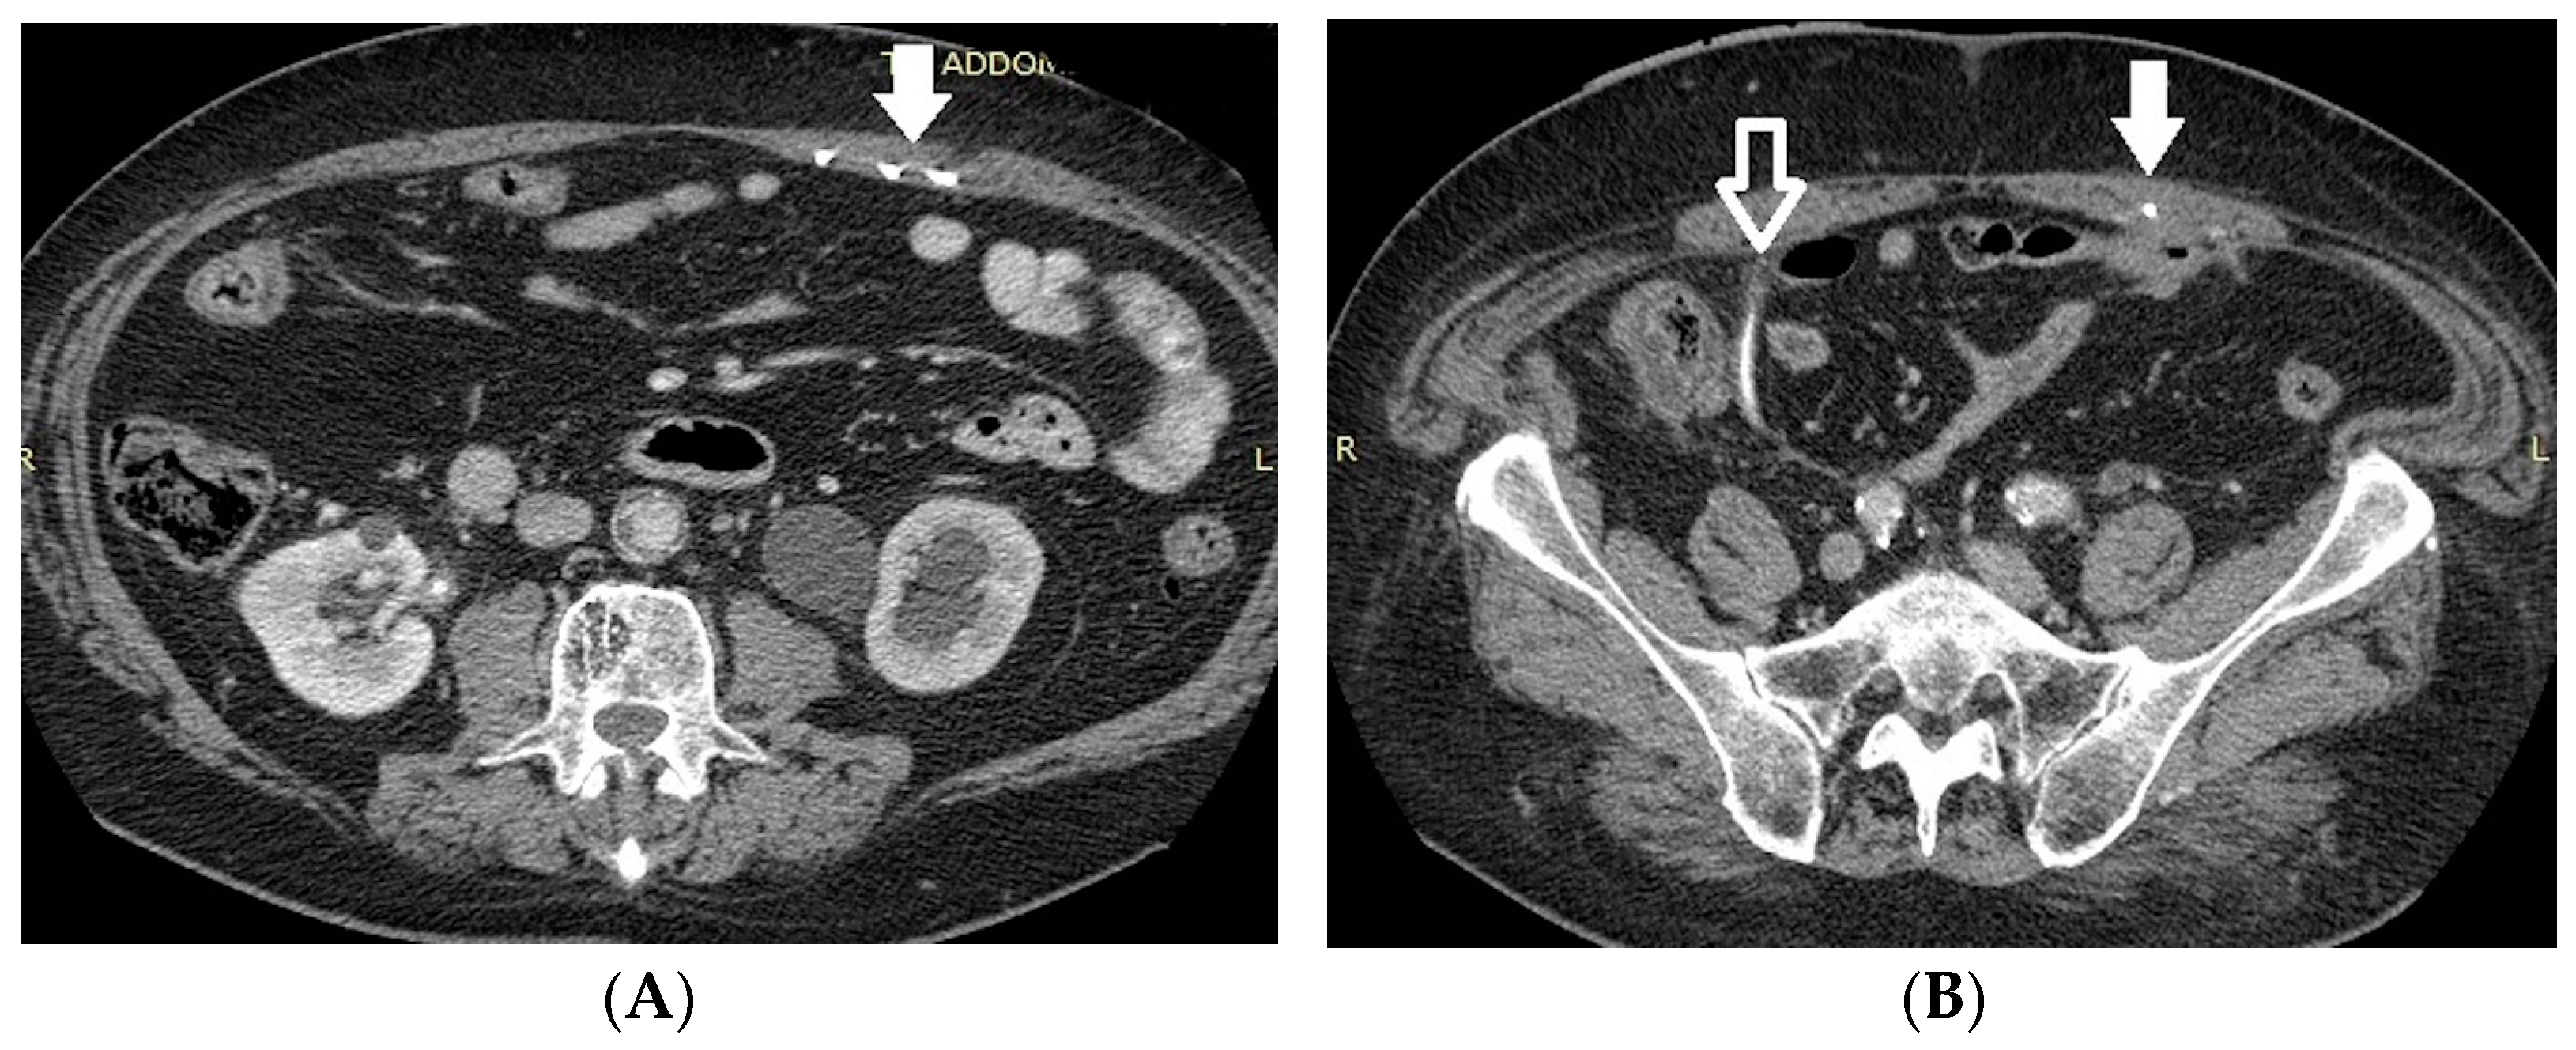

- Malposition: The malposition of a stent is defined as an incorrect position relative to initial placement, while displacement presents a subsequent occurrence in a device that was previously located in the correct position. A stent improperly positioned might assume a sub-pyelic position when the proximal end fails to reach the renal pelvis and a supravesical position when the distal end is detected within the ureter. The origins of this complication predominantly stem from the placement technique, whether it be endoscopy- or fluoroscopy-guided insertion. This underscores the need to verify the accurate positioning of the stent post-placement. Ensuring an adequate length is essential to reduce the occurrence of this complication (Figure 2, Figure 3, Figure 4, Figure 5 and Figure 6) [21,22].